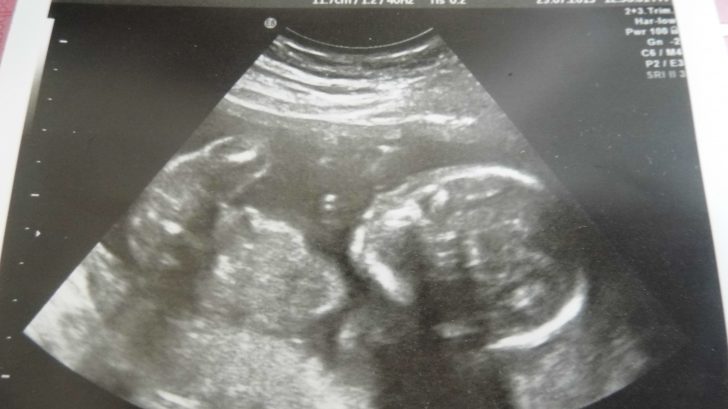

Díky tomu, že ted jsem doma a netrpělivě ošekávám svého prvního potomka, dokážu si užívat i odpočinku, a tak ráda chodím s bříškem na procházky po okolí a ráda pozoruji maminky s kočárky, důchodce, jak krmí holuby ale i pro někoho naprosto nepřípustné věci. Jednou jsem se setkala s názorem, že postižené ženy by neměli mít děti. Ano, souhlasím, ale kde je ta strašně úzce křehká hranice, která toto určuje? Hranice která by určovala: toto je ještě přípustné a toto už ne?